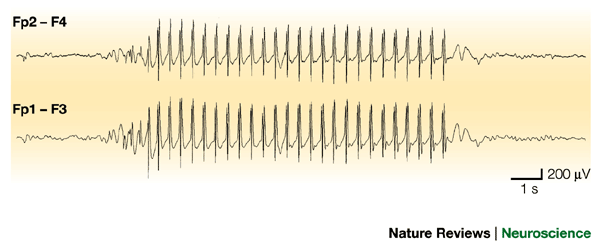

TYPICAL ABSENCE SEIZURE Childhood Absence Epilepsy (CAE) - Petit Mal Epilepsy - Pyknolepsy Childhood Absence Epilepsy | Epilepsy Foundation Frontiers | Absence Seizure Detection Algorithm for Portable EEG Devices | Absence Seizure Eeg